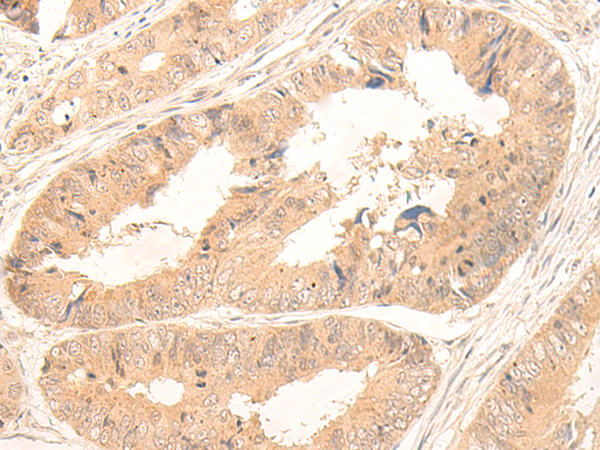

IHC (Immunohistochemisry)

(Immunohistochemistry of paraffin-embedded Human ovarian cancer tissue using FABP4 Polyclonal Antibody at dilution of 1:65(×200))